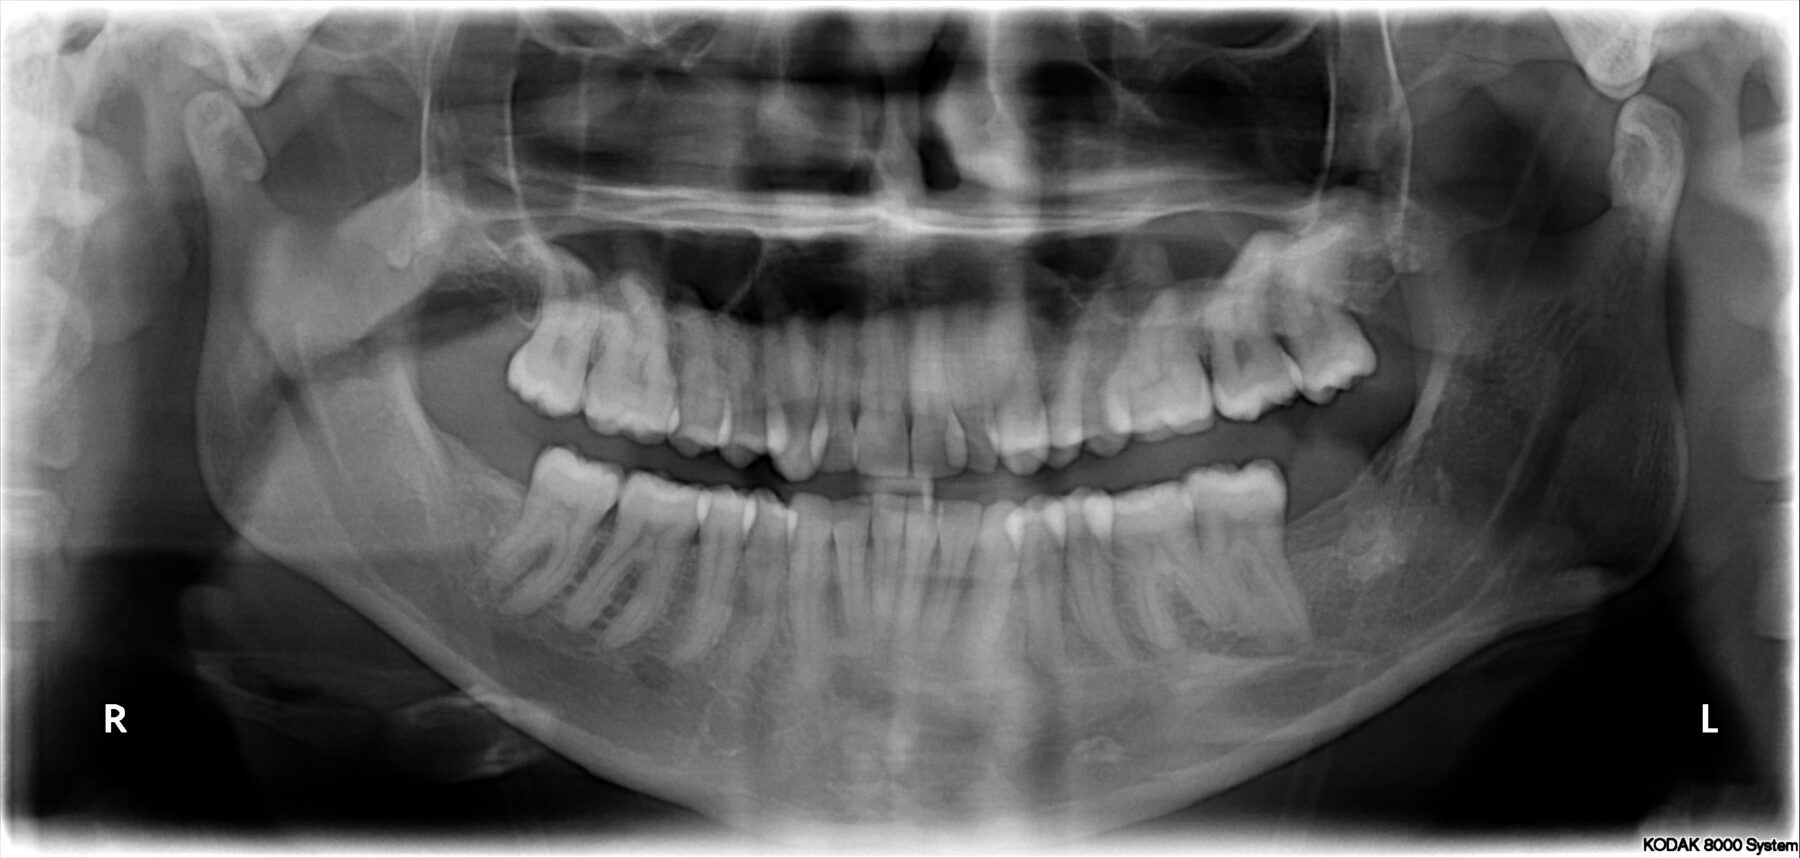

Als dit voor u bespreekbaar is, volgt eerst nog een vervolg-afspraak bij de orthodontist om ‘documentatie’ te maken. Dat betekent een scan van uw gebit, lichtfoto’s en röntgenfoto’s. De orthodontist zorgt ervoor dat de kMKA-chirurgen ook deze (röntgen)foto’s ter beschikking krijgen en laat de scan van het gebit uitprinten in 3D en neemt dat 3D model mee naar Frisius MC Leeuwarden.

Om dit resultaat te krijgen worden vaak eerst de tanden en kiezen “in de rij” gezet door enige tijd een beugel te dragen. Deze beugel wordt door de orthodontist aangebracht. Ook tijdens en na de operatie moet de beugel vaak nog enige tijd worden gedragen totdat het operatieresultaat de nodige stabiliteit bereikt heeft. Bij de behandeling zijn een orthodontist en een MKA-chirurg betrokken. Deze behandeling wordt dus in teamverband voorbereid en uitgevoerd. De gehele orthodontisch-chirurgische behandeling duurt ongeveer anderhalf tot twee jaar. De operatie vindt plaats tijdens de orthodontische behandeling, op ongeveer 2/3 ervan.